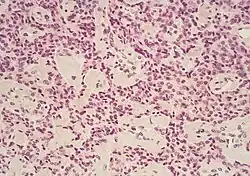

Micrograph of pancreatic ductal adenocarcinoma (the most common type of pancreatic cancer), H&E stain

The most common form of pancreatic cancer (adenocarcinoma) is typically characterized by moderately to poorly differentiated glandular structures on microscopic examination. There is typically considerable desmoplasia or formation of a dense fibrous stroma or structural tissue consisting of a range of cell types (including myofibroblasts, macrophages, lymphocytes and mast cells) and deposited material (such as type I collagen and hyaluronic acid). This creates a tumor microenvironment that is short of blood vessels (hypovascular) and so of oxygen (tumor hypoxia).[2] It is thought that this prevents many chemotherapy drugs from reaching the tumor, as one factor making the cancer especially hard to treat.[2][3]